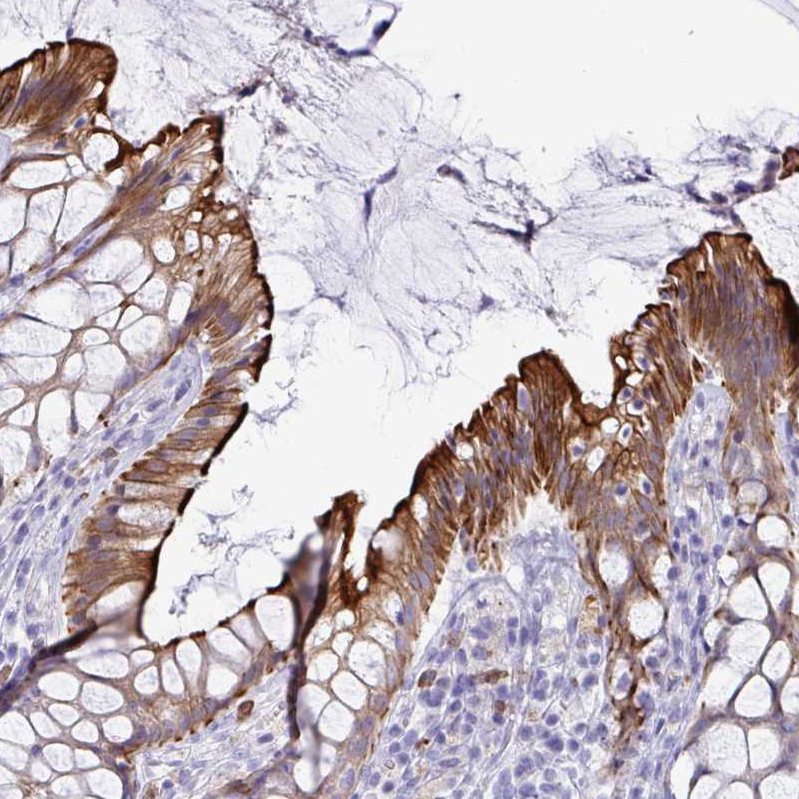

Immunohistochemical staining of human rectum shows strong membranous and cytoplasmic positivity in glandular cells.